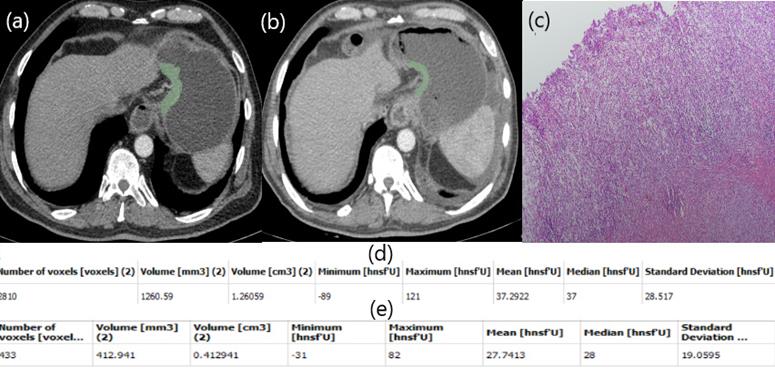

In our study, a patient with low HU alteration had pathologically high fibrosis (Figure 2), while another patient with high HU alteration did not respond well to chemotherapy and fibrosis was almost nonexistent (Figure 3). The aim of this study is whether HU alterations can help evaluate the response to chemotherapy in patients with gastric cancer who receiver NAKT. As a matter of fact, at the end of our study the difference in HU alteration being minor was found to be associated with a good pathological response (Figure 2). The relation between HU alteration and histological changes in the tumor bed may be the subject of another study.

Patient responding well to NAC. Free hand circular ROIs covering the same region of pre (a) and post (b) treatment. HU values pre (d) and post (e) NAC. Diffuse fibrosis in pathology specimen (c).

Patient responding poorly to NAC. Free hand circular ROIs covering the same region of pre (a) and post (b) NAC. HU values pre (d) and post (e) NAC. Postop pathology specimen. Almost no fibrosis (c).